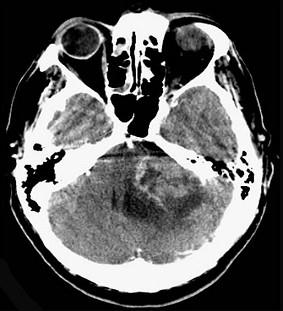

问题 听神经瘤(如图所示)的最常见症状为()

选项 A.头痛、呕吐 B.面部麻木,痛觉减退 C.眩晕,单侧耳鸣,耳聋 D.吞咽困难,进食呛咳 E.小脑运动共济失调

答案 C